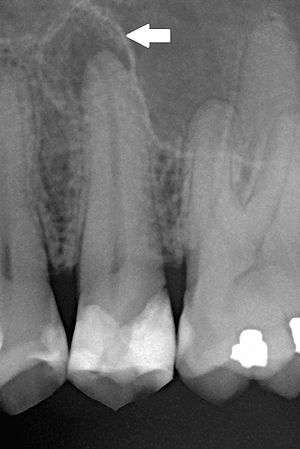

| Periapical dental radiograph showing chronic periapical periodontitis on the root of the left maxillary second premolar. Note large restoration present in the tooth, which will have undergone pulpal necrosis at some point before the development of this lesion. | |

The radiographic features of periapical inflammatory lesions vary depending on the time course of the lesion. Because very early lesions may not show any radiographic changes, diagnosis of these lesions relies solely on the clinical symptoms . More chronic lesions may show lytic (radiolucent) or sclerotic (radiopaque) changes, or both.